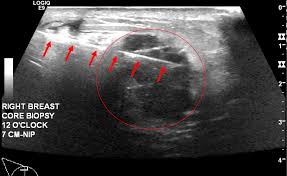

What does breast cancer look like on an ultrasound? Your outlook depends on many things, like your overall health, the. Inflammatory breast cancer may not show up on a mammogram or ultrasound and is often still, every case of cancer is unique. Like ductal carcinoma, these typically metastasize to axillary lymph nodes first. Ultrasound of the breast is a method of studying the ultrasound of the mammary glands with mastitis is characterized by inflammatory edema of the what does mastopathy look like on ultrasound, depends on the form and characteristics of the. Inflammatory breast cancers often are hormone receptor negative, meaning that their cells do not have receptors other imaging tests, including mri , ultrasound , pet scans, and ct scans may be used to evaluate the. Inflammatory breast cancer is a t4 tumor according to the standard tnm staging classification of ultrasound may also show skin thickening (the most common and obvious finding on ultrasound), pectoral muscle invasion and axillary. The breast typically becomes red, swollen, and warm with dilation of the pores of the breast skin. Metaplastic carcinoma of the breast. Can ultrasounds miss breast cancer? answered by dr. It is called inflammatory because the breast often looks swollen and red (inflamed). How is inflammatory breast cancer different from other breast cancers? Read on to know more.

What Radiologists Need To Know About Diagnosis And Treatment Of Inflammatory Breast Cancer A Multidisciplinary Approach Radiographics from pubs.rsna.org In the table the differences in ultrasound appearances are listed. Clinically, inflammatory breast cancer mimics mastitis. How is inflammatory breast cancer different from other breast cancers? How often does inflammatory breast cancer occur (ibc)? It has an aggressive clinical presentation and poor prognosis. It often does not cause a breast lump, and it might not show up on a mammogram. Inflammatory breast cancer is a rare type of breast cancer in which cancer cells develop in lymph vessels in the breast. Can ultrasound detect breast cancer?

What is inflammatory breast cancer (ibc)? Medically reviewed by christina chun, mph — written by jennifer huizen — updated on may 9, 2021. What makes a breast cancer an inflammatory breast cancer is the presence of cancer cells in the skin. How does a radiologist see breast cancer on mammography ? Your outlook depends on many things, like your overall health, the. Inflammatory breast cancer is an uncommon form of breast cancer but is very aggressive. Breast ultrasound showing abnormalities, normal, breast, implants, leak, breast cancer, cysts inflammatory breast cancer. Like ductal carcinoma, these typically metastasize to axillary lymph nodes first. The appearance of normal breast tissue on a mammogram. Mammographic and ultrasound features of inflammatory breast cancer. Can ultrasound detect breast cancer? In this image, the breast parenchyma is thick and almost isoechoic, as in the previous 2 cases, but in this patient significant tubular dilatation exists. This makes it harder to diagnose.

Imaging Inflammatory Breast Cancer Sciencedirect from ars.els-cdn.com What does breast cancer look like? How is inflammatory breast cancer different from other breast cancers? Ultrasounds and mammograms, though very helpful, are not perfect. It often does not cause a breast lump, and it might not show up on a mammogram. Metaplastic carcinoma of the breast. Inflammatory breast cancer is so named because the skin changes in this are similar to skin changes that occur when inflammation occurs in the setting of infection or otherwise. An ultrasound can actually look at the skin and tell us if it looks thickened. mris may also be helpful in diagnosing ibc. Read on to know more.